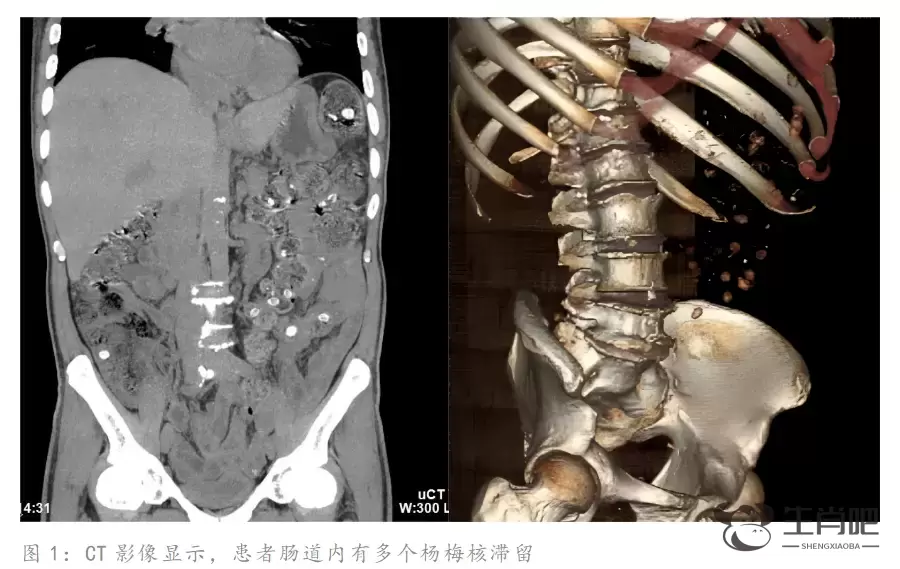

根据CT影像报告显示,郑师傅的肠道内存在多处类圆形高密度致密影。密密麻麻的圆圆小点正是滞留在肠道内的杨梅核,这是导致他腹痛难忍的罪魁祸首。

急诊医生介绍,肠道内有大量杨梅核,很有可能引发胃肠道痉挛和肠梗阻。经药物治疗,郑师傅肠道内的杨梅核于次日排出体外,疼痛随即缓解。